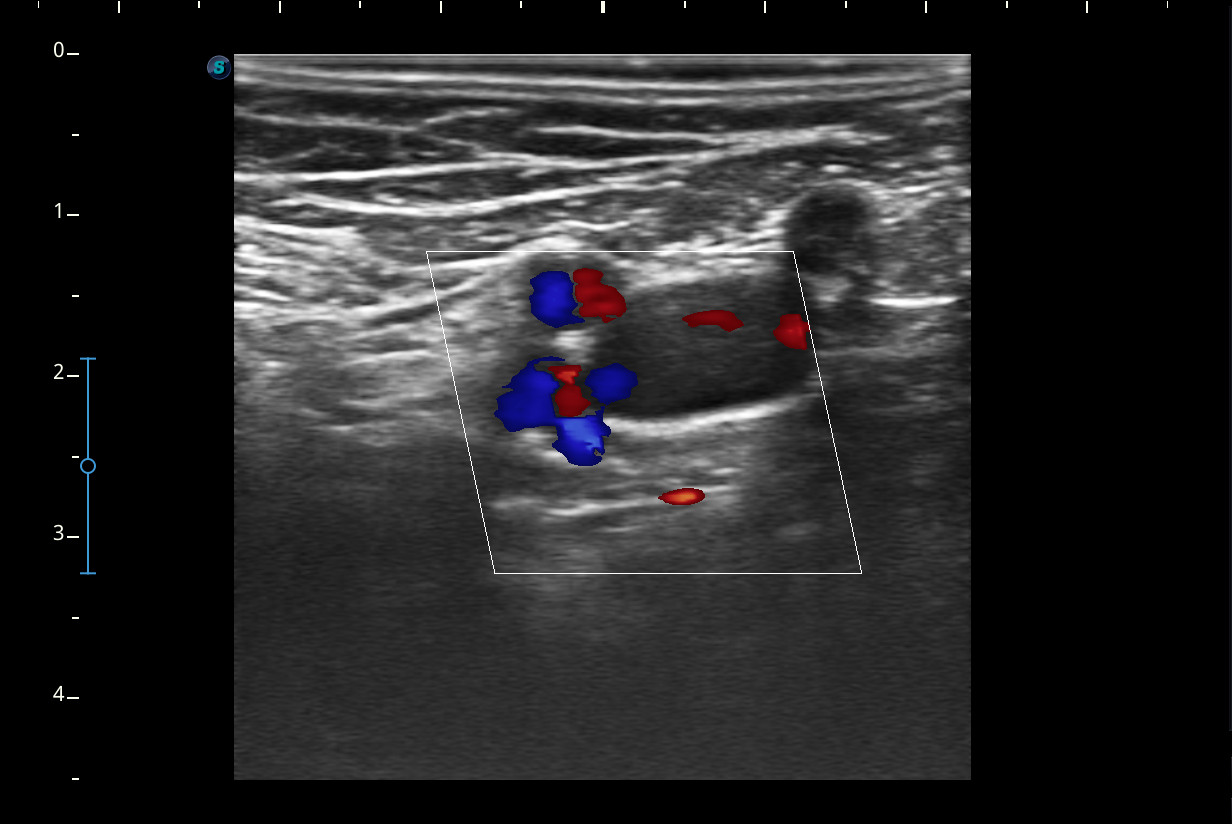

A nivel del hueco poplíteo se visualiza presencia de trombosis de la vena poplítea, no así en localizaciones proximales.Otras pruebas complementarias realizadas (si existen)